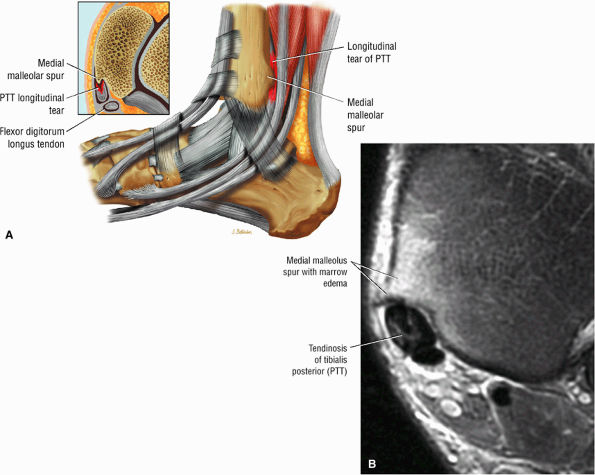

Type 1: There is tendon hypertrophy with heterogeneous signal intensity in intrasubstance vertical splits (Fig. 5.130). Associated findings include increased signal intensity (intrasubstance striations) and girth at the distal tendon insertion to the navicular (a normal variant), osseous spurring with or without fatty marrow signal in the posteromedial aspect medial malleolus (see Fig. 5.130), and tendon dysfunction or dislocation with disruption of the flexor retinaculum (Fig. 5.131).

Associated medial malleolar spur may contribute to tendon degeneration.